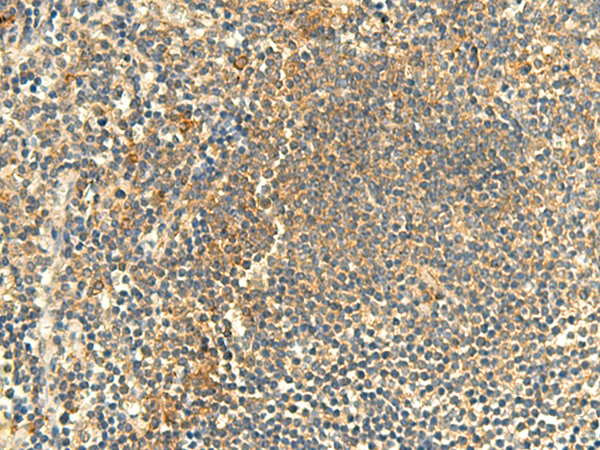

分类: 科研抗体货号: P07187别名: KIP1; MEN4; CDKN4; MEN1B; P27KIP1应用: WB,IHC反应种属: Human, Mouse